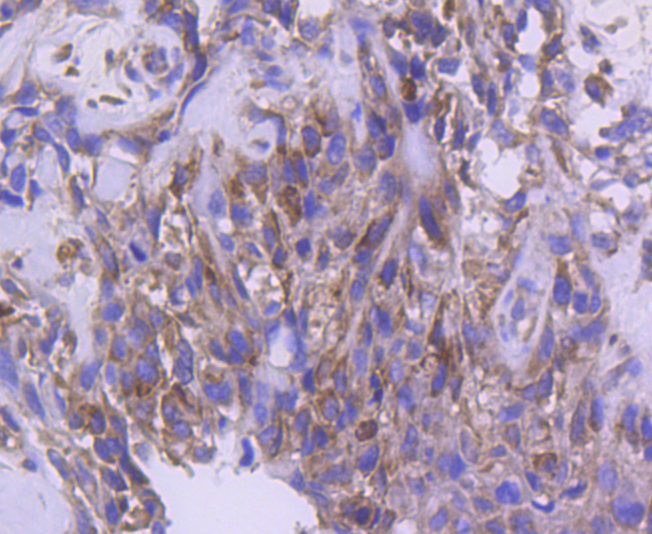

IRF5 Rabbit mAb

WB, IHC, FC

WB: 1:1,000-5,000

IHC: 1:50-1:200

FC: 1:50-1:100